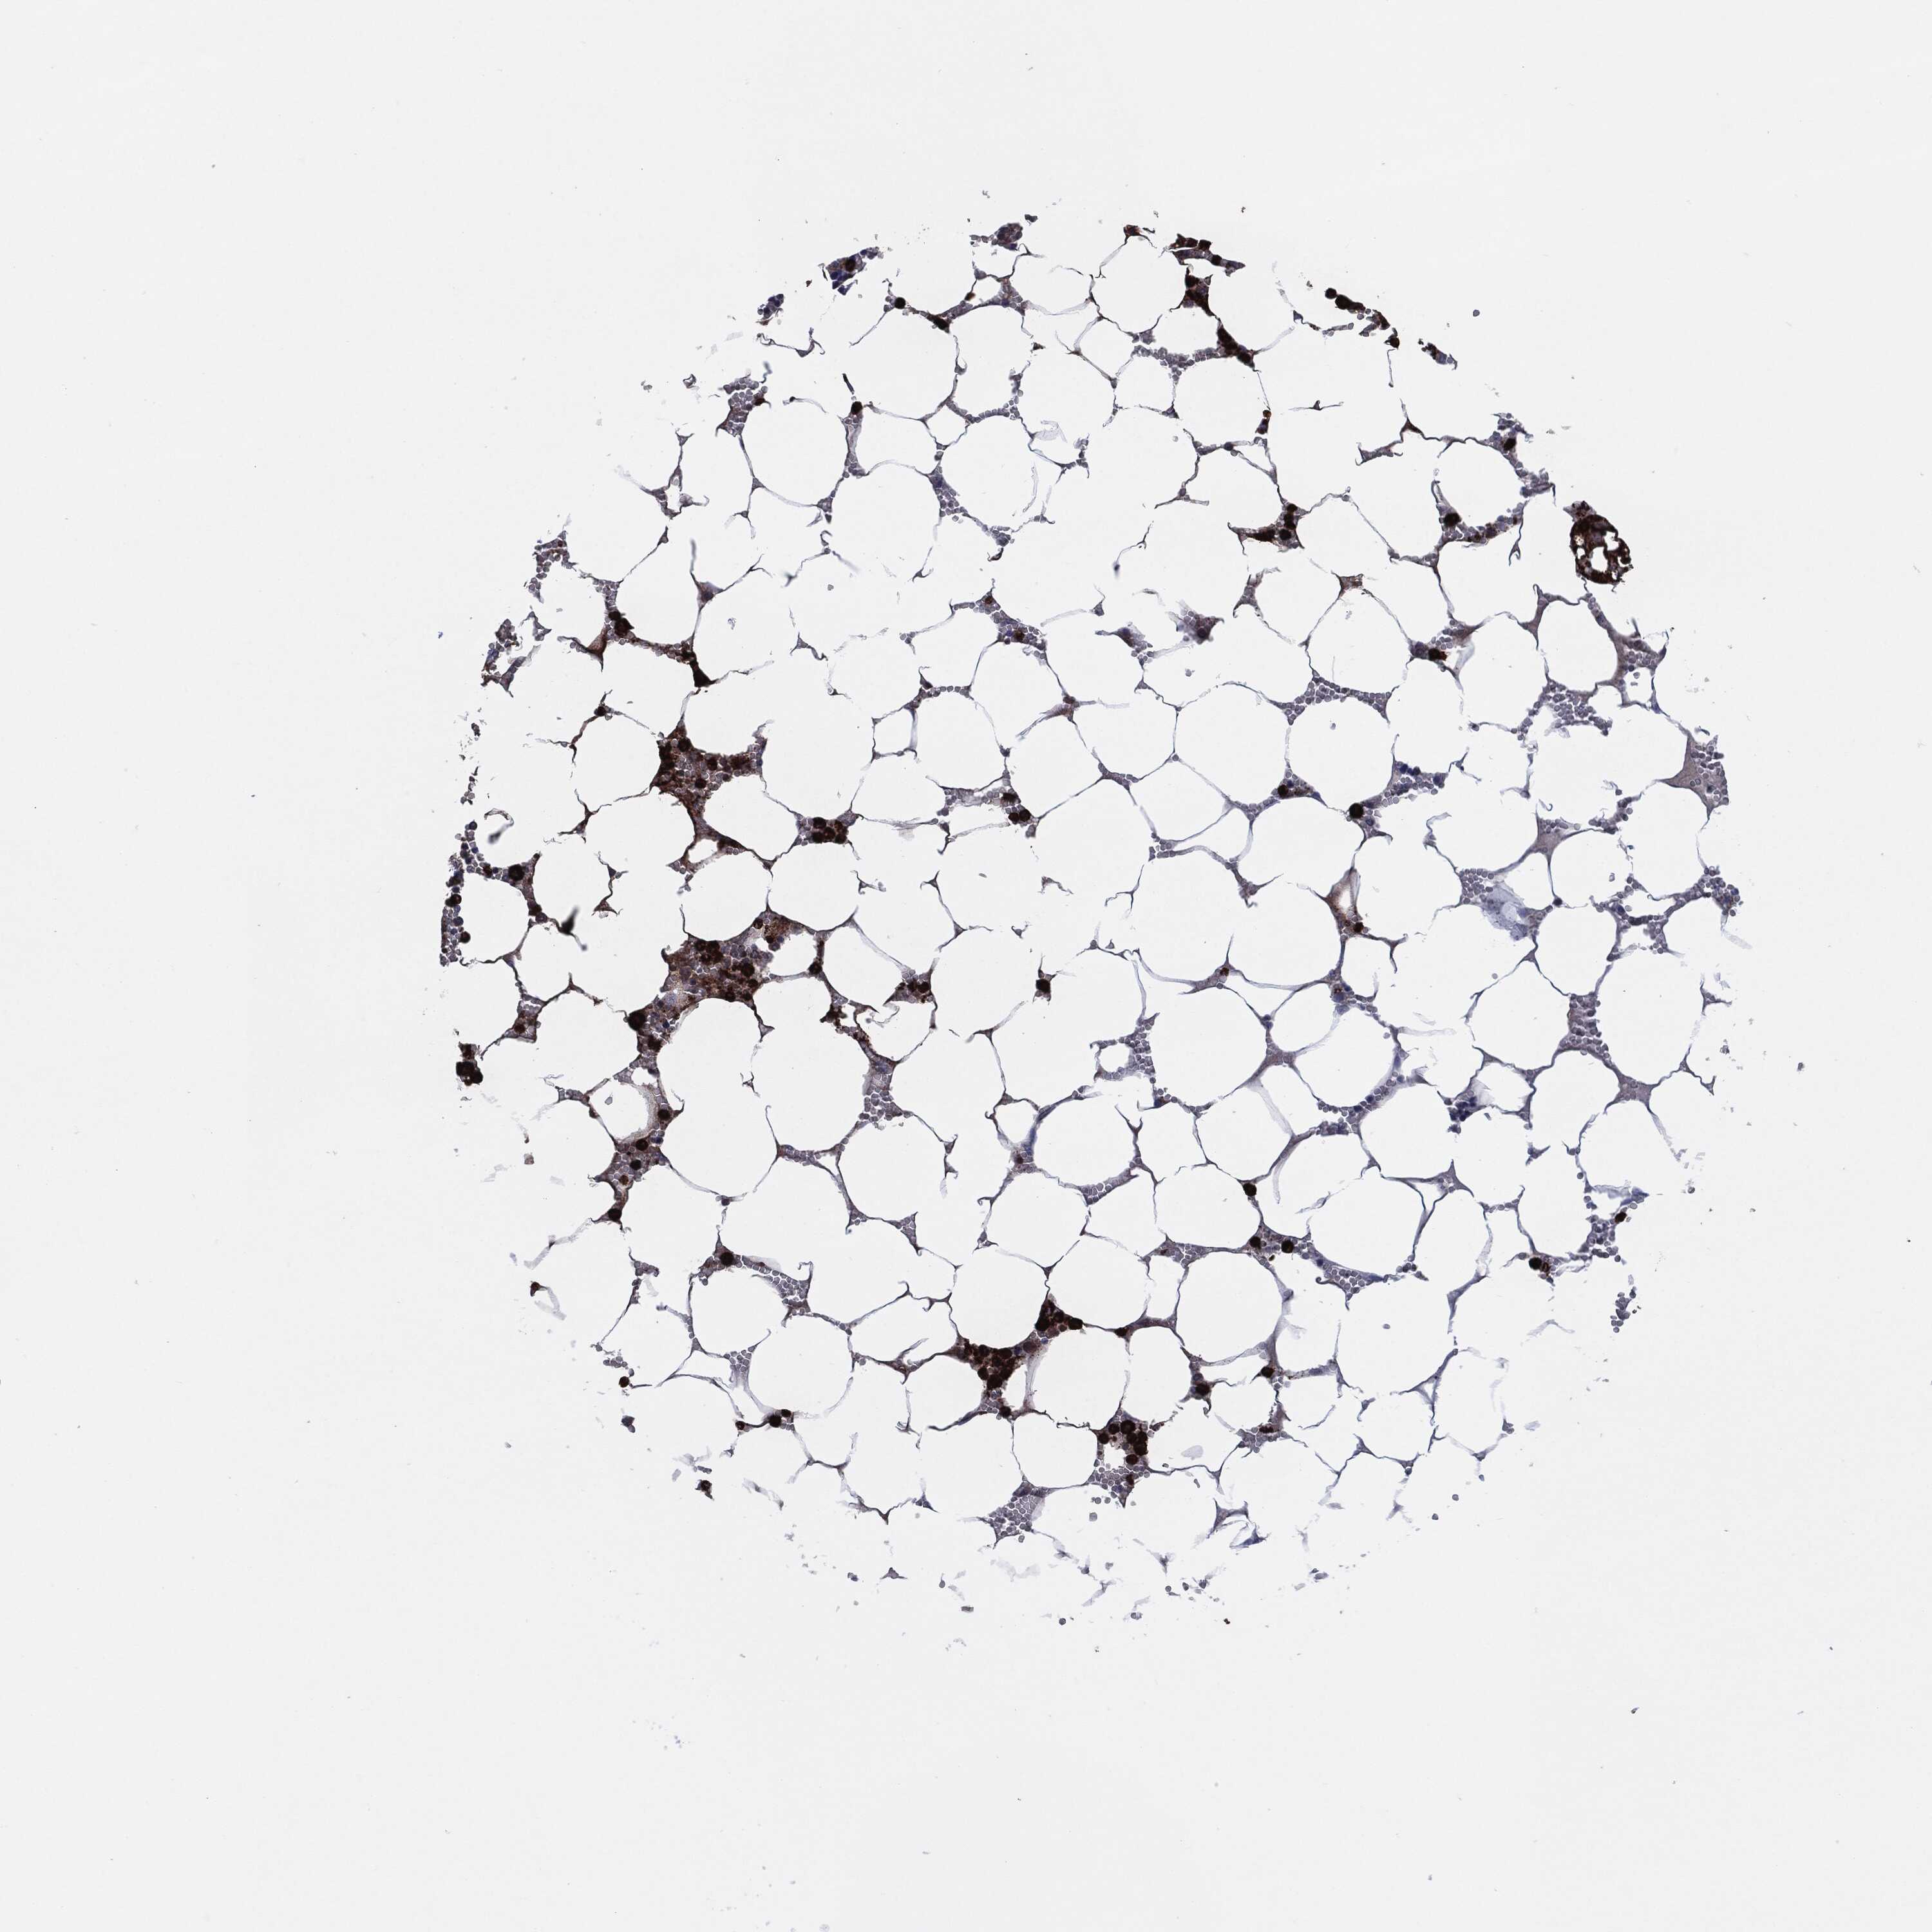

BONE MARROW - Antibody stainingi

Antibody staining in the annotated cell types in the current human tissue is reported as not detected, low, medium, or high, based on conventional immunohistochemistry profiling in selected tissues. This score is based on the combination of the staining intensity and fraction of stained cells.

Each image is clickable and will lead to virtual microscopy that enables deeper exploration of all samples and also displays staining intensity scores, fraction scores and subcellular localization as well as patient and tissue information for each sample.

Antibody HPA021147Antibody HPA061464Antibody CAB000059Antibody CAB080352Antibody CAB080353Antibody CAB080354

Hematopoietic cells LowHighMediumHighHighHigh